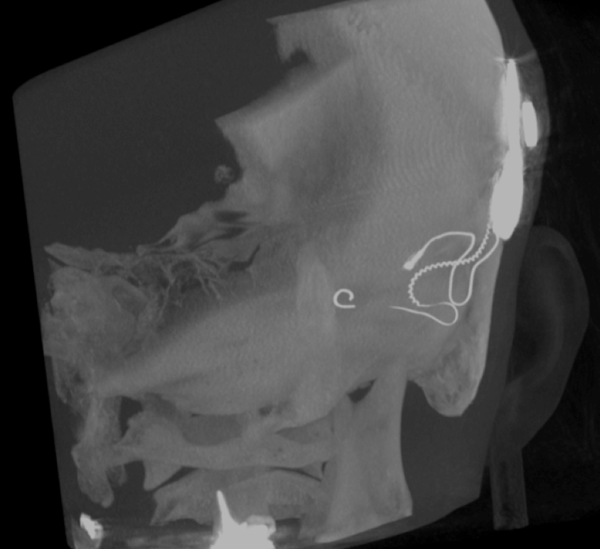

Both patients were imaged immediately with CBCT using SCANORA® 3Dx (Soredex, Tuusula, Finland). The field of view (FOV) was 140 x 165 mm and voxel size 0.2 mm. Imaging parameters were 90 kV, 8 mA, 4.00s. Standard 1 mm axial, coronal and sagittal reformations were made, as well as MIP and 3D reconstructions using OnDemand3D™ software (Cybermed, Seoul, South Korea).

CBCT proved to be optimal for imaging of these implants because of the superior bony delineation and nearly artefact free images. All four parts, i.e. the receiver stimulation part, extracochlear electrode implanted on the surface of the temporal bone, the extracochlear electrode plate and the intracochlear electrode array could be well imaged with CBCT.

On CBCT all four of the important parts of the implant were very well seen both on the axial slices and three dimensional surface reconstruction images. The implant is placed on magnetic plates, and the extracochlear part was seen in an abnormal separated position. The intracochlear electrode array showed no signs of separation in either of the cases. The intracochlear electrodes were well seen in both of the cases.

The optimal images of these two patients are shown in the radiographic illustrations in Figures 1-7.

Figure 2: 3D MIP image of patient 1.